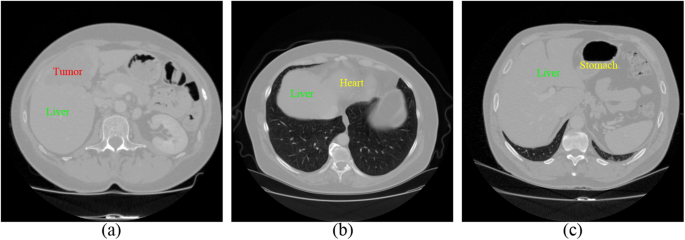

However, some factors in CT images bring some challenges to liver segmentation. First, imaging artifacts and tumor pathologies often result in intensity inhomogeneity. Therefore some standard approaches depending on gray-value only, may not be sufficient for this case. Second, intensities of several adjacent organs like heart and stomach are very similar to liver tissue itself. In Fig. 1, some examples of these difficulties are given. Multi-dimensional features and shape priors can aid to separate the neighboring organs with similar intensities and reach the desired boundaries of the structures.

Examples of the limiting factors for liver segmentation in CT images. (a) Demonstrates intensity inhomogeneity between liver and tumor. (b) and (c) display that liver, heart, and stomach share similar intensity value.